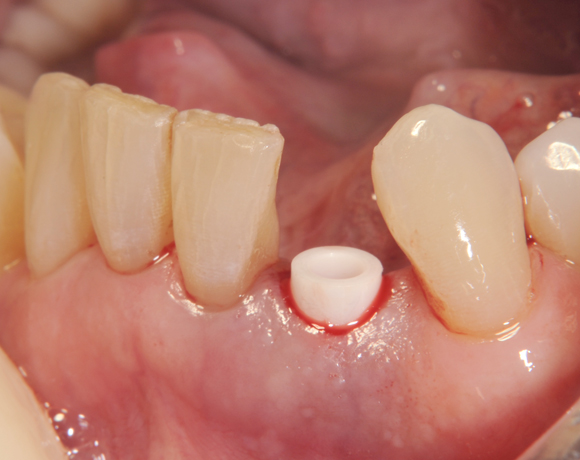

Am Beispiel dieses Patientenfalls wird gezeigt wie ein Einzelimplantat für den Unterkieferfrontzahn 33 eingesetzt wird.